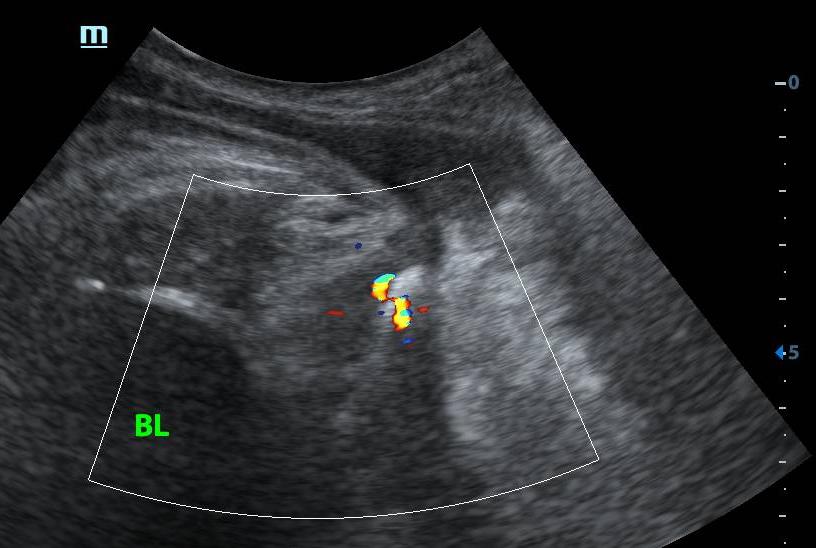

李四倒也听话,脱下裤子配合检查,我先尝试用线阵(浅表)探头经会阴看。

发现个小东西,约0.4x0.2cm,一上血流还有闪烁伪像。

放大深度,扩大扫查后,“嗯?居然还有个大的,大小约1.0x0.6cm”远场实在看不清,换凸阵(腹部)探头。

破案了。

后尿道结石嵌顿。报告怎么写呢???交给你了,你来写。。。